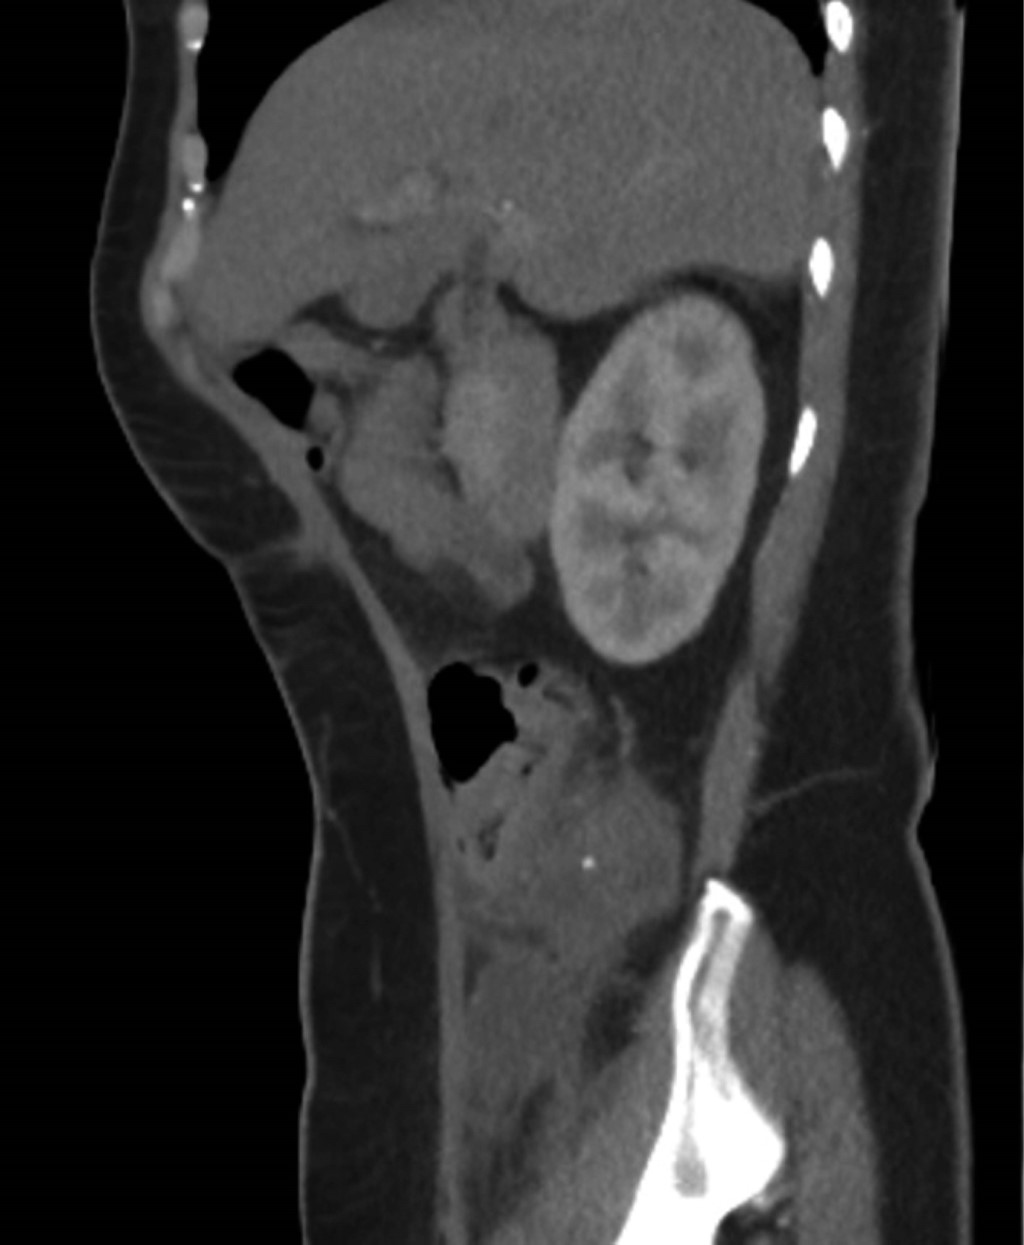

A simple and contrasted abdominopelvic CT scan on 03/11/22 showed a sub and retrocecal collection of 50 cm3 with a peripheral inflammatory process, suggesting a complicated appendicular process (Figures 1 and 2).

The literature reports a female predominance and a peak presentation between the fifth and sixth decade of life on average, as in our patient. There is no established test for diagnosis. However, in ultrasonography studies, a hypoechoic lesion can be observed, while in tomography, the images are hypodense and homogeneous, like "onion layers", sometimes with cystic areas inside or with calcified walls many times adjacent to the cecum.7 If the appendix measures ≥ 15 mm in its transverse diameter, a mucocele should be suspected with a sensitivity of 83% and specificity of 92%.8

The imaging test of choice is computed tomography, which is diagnostic in less than 50% of the cases.1 Although, in the first instance, the diagnostic suspicion in our patient was acute appendicitis and not a mucinous tumor of the appendix, computed tomography -which is considered the best imaging study in both pathologic entities- was an essential diagnostic complement in the approach; however, it was not conclusive. The irregularity in the appendiceal wall and increased soft tissue thickness may predict tumor malignancy.8

Figure 1

Figure 2